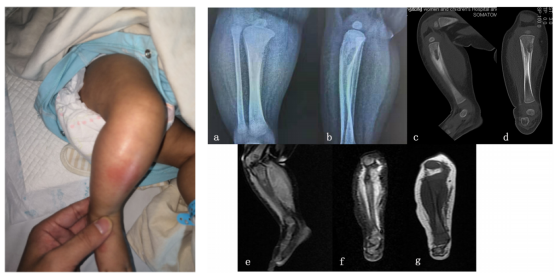

图2. (a-b)X射线显示胫骨近端有溶解性病变和骨膜反应。(c-d)CT冠状面和矢状面显示胫骨干骺端有虫蛀样、不规则侵蚀。(e-g)MRI显示胫骨近端有一个T1低信号区域,对应于T2加权像上的高信号区域和一个大的骨膜下脓肿

胫骨的X射线检查显示边界不清、不规则的骨溶解和虫蛀图案,并显示胫骨近端干骺端的骨膜反应,并伴有邻近的新骨形成。冠状面和矢状面的计算机断层扫描(CT)显示胫骨干骺端有虫蛀和融化的征象以及不规则侵蚀。横断面CT显示大面积骨皮质病变、边界模糊和层状骨膜反应。胫骨磁共振成像(MRI)显示胫骨近端有一个T1低信号区域,对应于T2加权像上的高信号区域和一个大的骨膜下脓肿。MRI显示骨膜水肿、骨膜增厚和邻近肌肉水肿(图2)。